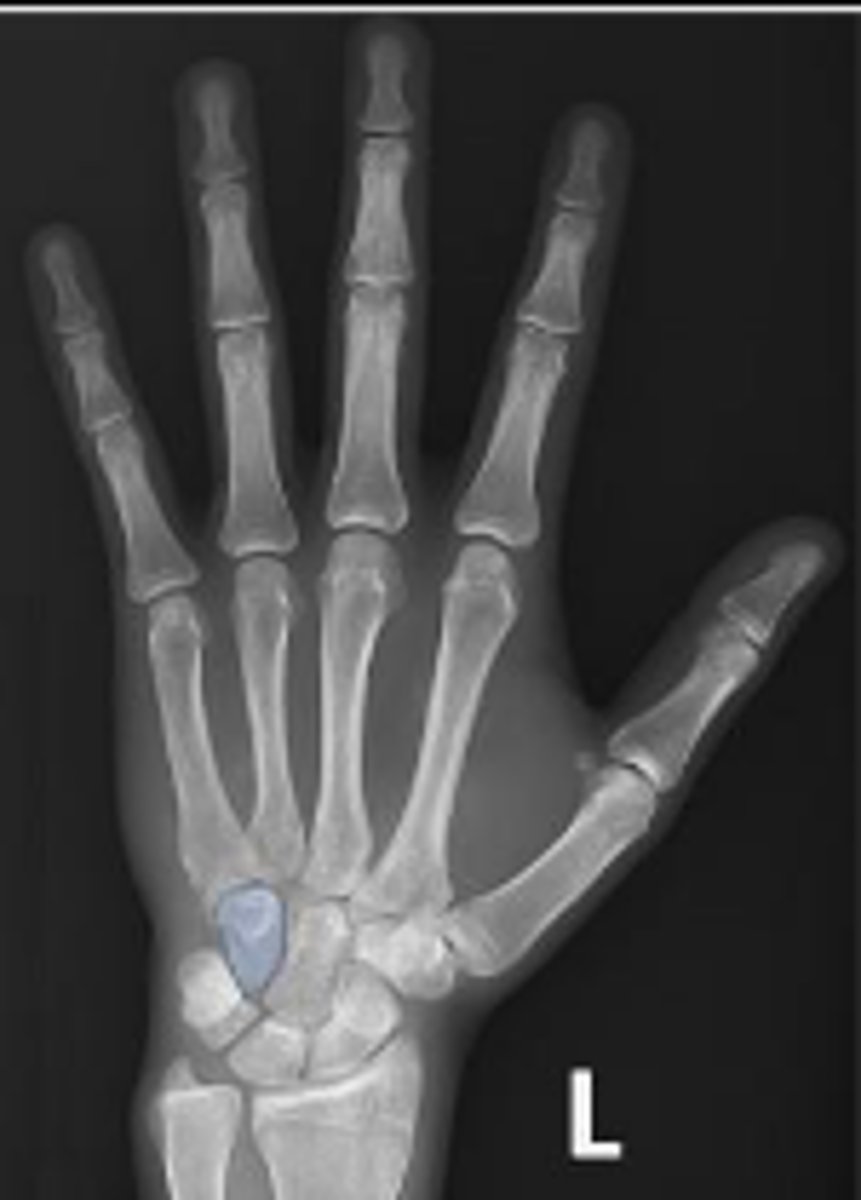

PA of the left hand

What is the name of the radiographic view?

Left scaphoid

What is outlined?

Left capitate

Left hamate

Left trapezium

What is the arrow pointing to?

Left triquetrum

Styloid process of the left ulna

Left lunate